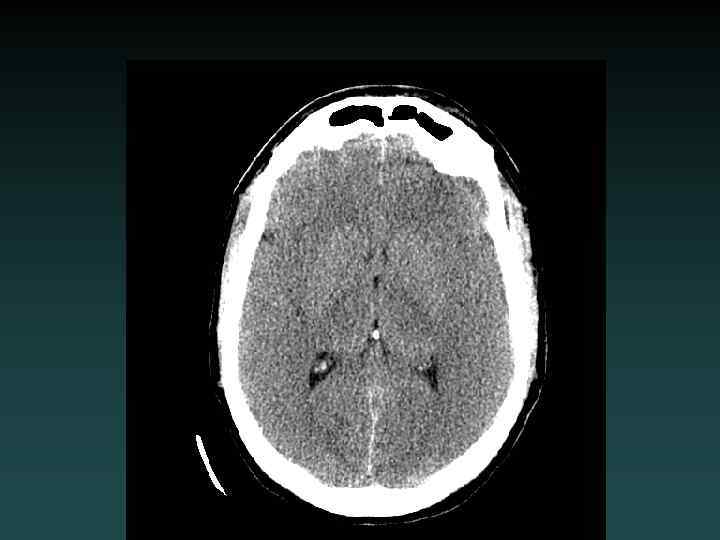

Intracerebral Hemorrhage • Hypertension – Most common – Characteristic Locations • IF LOBAR BLEED: – – SEARCH for underlying cause! MRI/MRA/MRV DSA or CTA Repeat imaging if negative initially • Look for: – EXPANSION – UNDERLYING LESION

Parenchymal Hemorrhage with Ventricular Extension